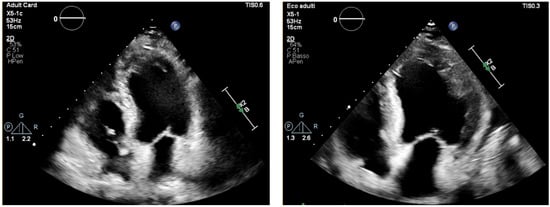

During the acute phase, TTE is important for assessing global cardiac function, through the left ventricular (LV) ejection fraction (EF). However, findings may be normal or slightly abnormal, such as hypokinesia, subendocardial hyperechogenicity, chamber dilation or increased wall thickness (pseudohypertrophy) [] (Figure 2).

Figure 2.

Transthoracic echocardiography, apical four-chamber view. Normal LV thickness and size (left), becoming pseudo-hypertrophic and hypokinetic after onset of eosinophilic myocarditis (right).